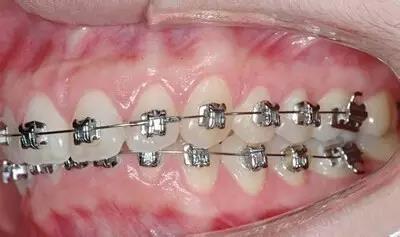

1、金属矫治

牙套黏在牙齿的唇面,就是常见的“小钢牙”,在张嘴说话或者大笑的时候就能够被外人看到。